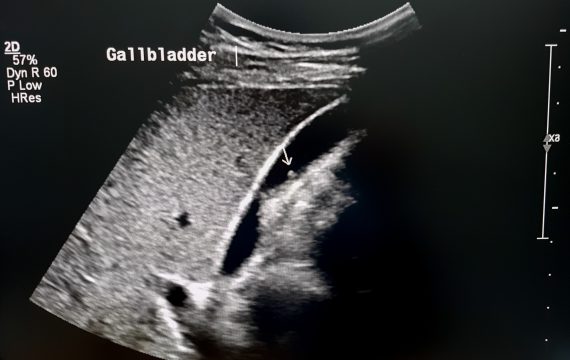

Why Your Gallbladder Matters Even Without “Typical” Pain

As an HPB (Hepato-Pancreato-Biliary) surgeon, I often meet patients who are surprised when they are told that they need gallbladder surgery (laparoscopic cholecystectomy). They haven't…